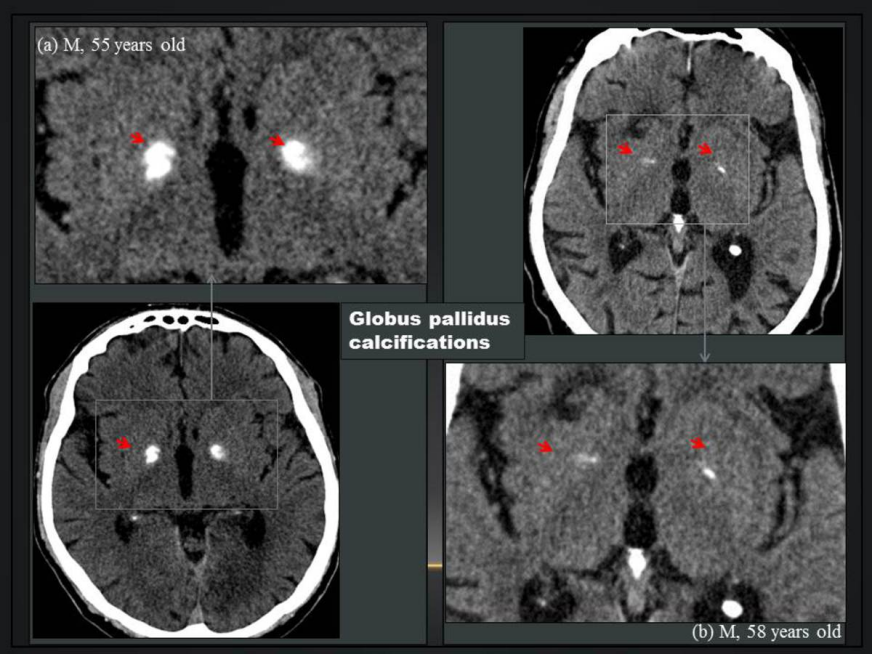

男,69 岁,大脑镰钙化呈条片状